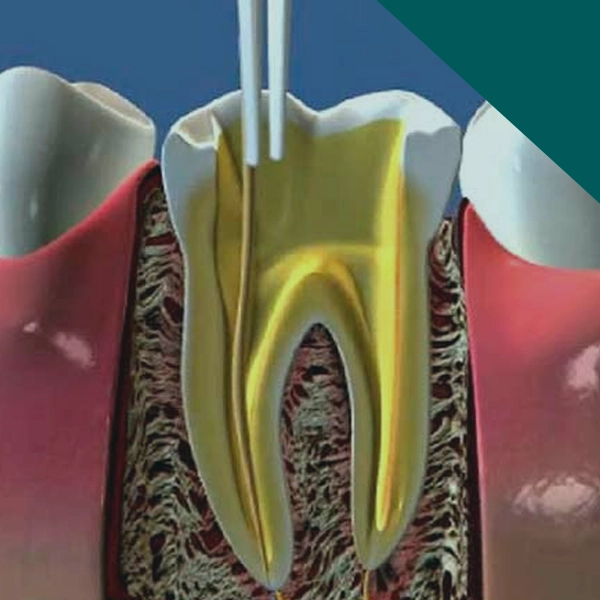

Endodontia

Tratamento de canal realizado com técnicas atuais e precisas para eliminar a dor, preservar o dente natural e recuperar sua função.